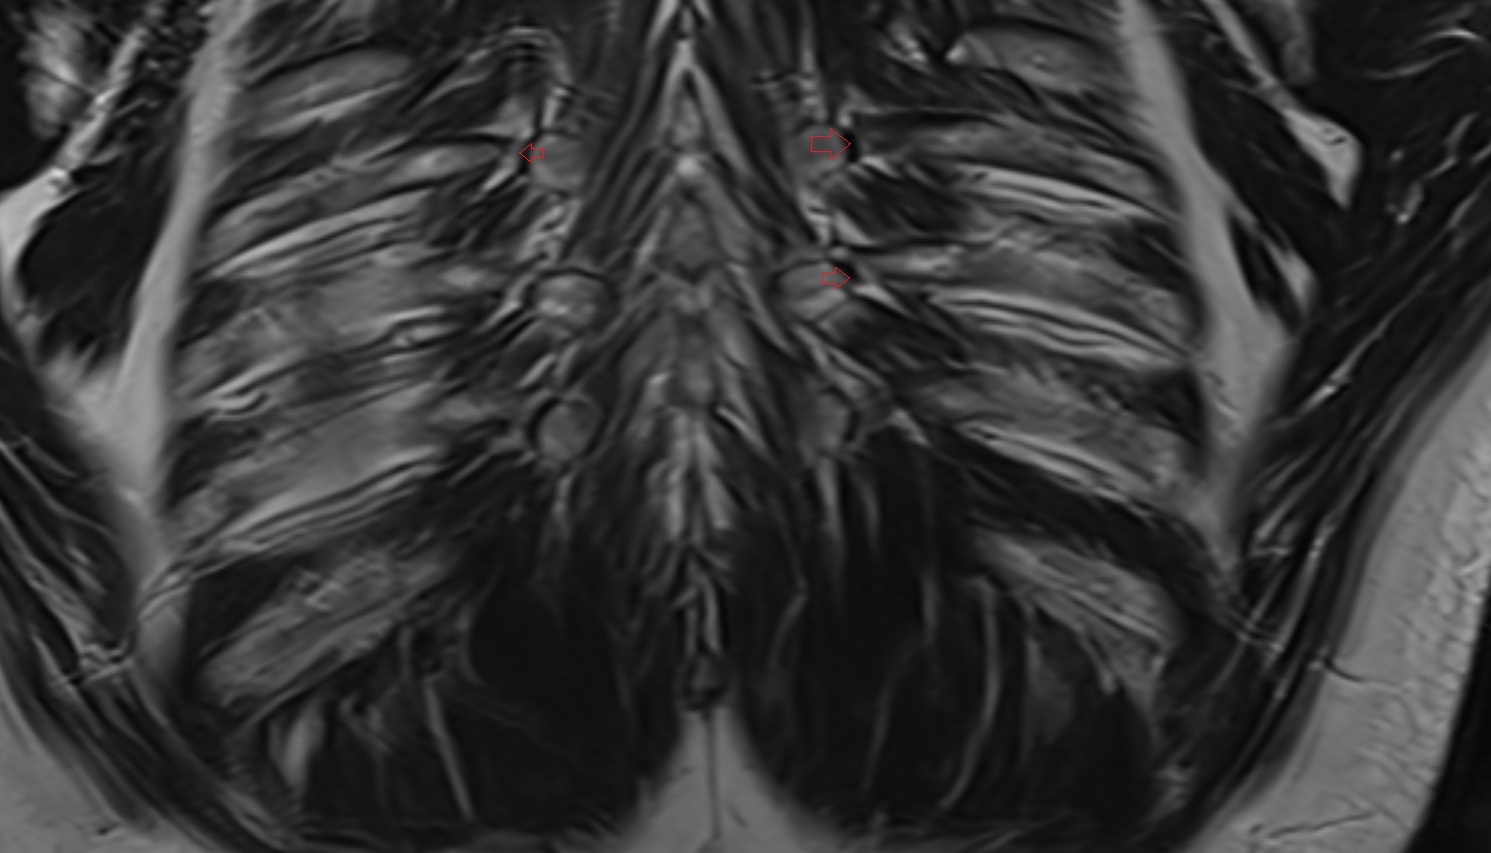

- Arbor Vitae (Cerebellar White Matter)

- Cerebellum

- White matter of cerebellum (Arbor vitae)